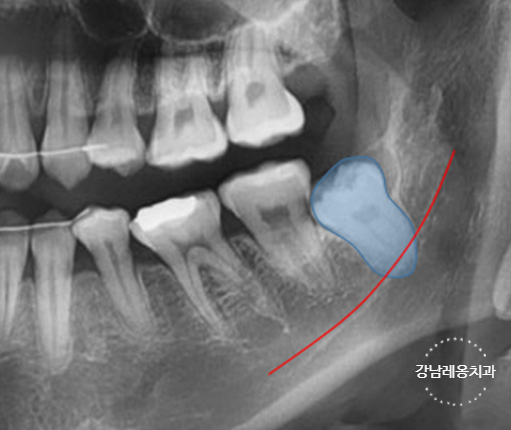

✅ 사랑니가 기울어져 있거나 누워있는지

✅ 옆으로 누워있는 수평 매복 사랑니

✅ 아래턱 신경과 매우 가까운 위치의 사랑니

고난도 케이스 경험 다수

최소절개

하루 발치 최대 60개

사랑니 발치로 강남레옹치과에 방문해주시는

40~50%가 수평/매복 사랑니이며

아래와 같은 고난도 케이스도

충분한 상담을 통해

사랑니 진료를 진행하고 있습니다.